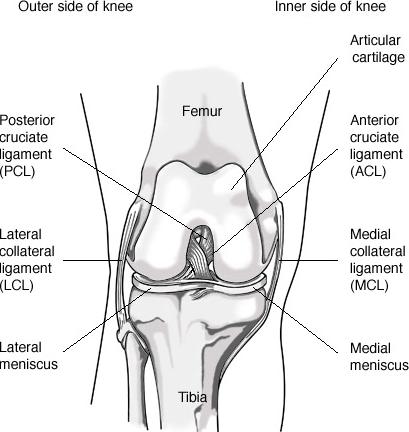

49_ligaments